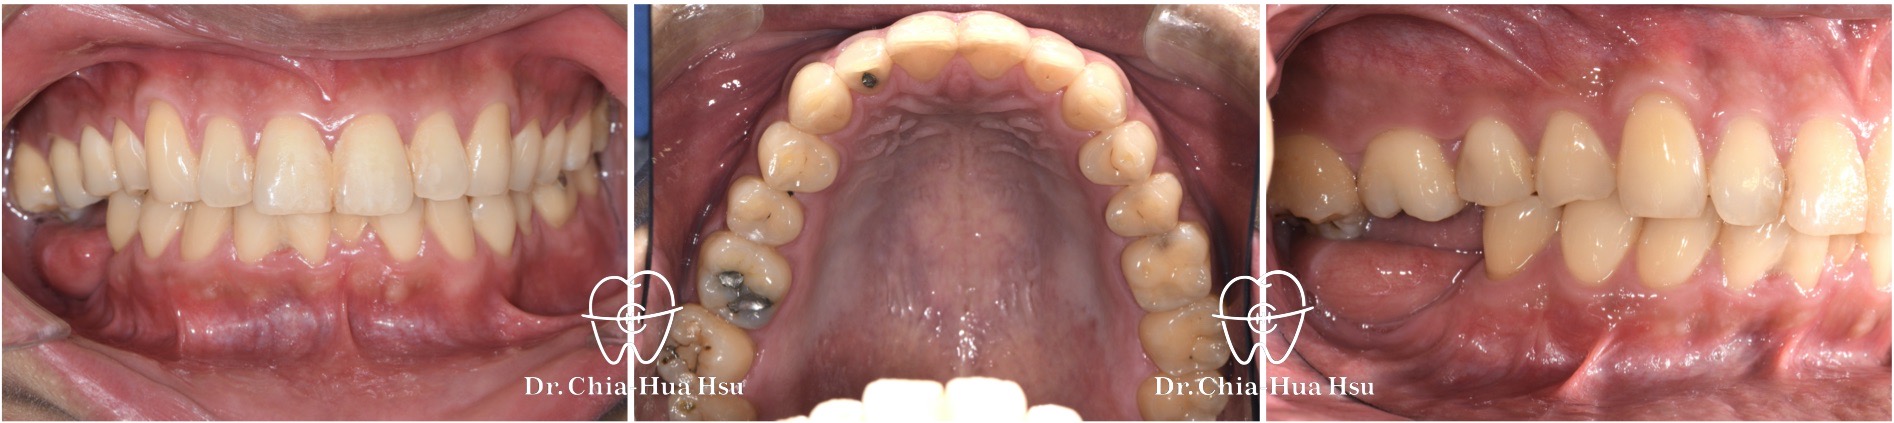

大臼齒過度萌發、長期缺牙

• 病患主訴:配合植牙與假牙製作,進行局部矯正治療。

• 問題分析:患者有齒列擁擠狀況,還有因長期缺牙導致大臼齒過度萌發的問題。

• 治療方式:使用局部金屬矯正器,搭配骨釘骨板,進行局部矯正治療。

• 治療時間:1 年。

• 治療結果:改善上顎大臼齒排列,提供足夠空間給下顎植牙與假牙製作。

治療前

治療後